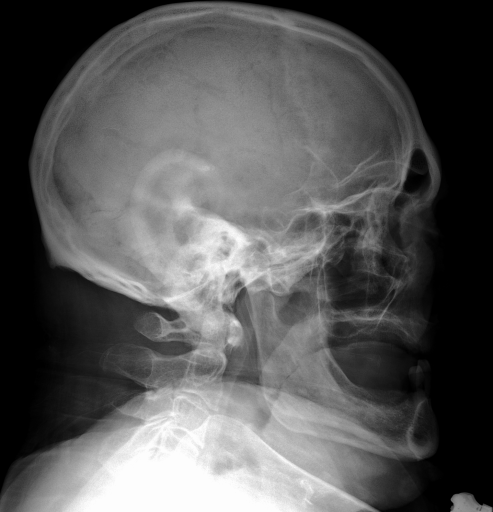

Details of the IRMA database is described in literature [24],[27],[25]. IRMA dataset offers 12,677 images for training and 1,733 images for testing. Figure 4 shows some sample images from the dataset long with their IRMA code in the format TTTT-DDD-AAA-BBB.